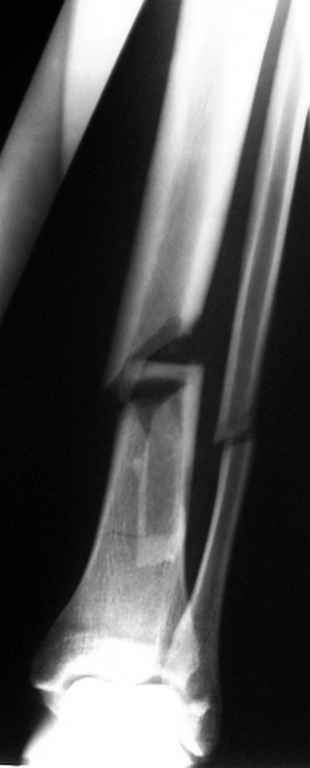

Консультировал рентгенограммы после интрамедуллярного остеосинтеза

бедра гвоздем Fixion. Пациенту объяснили, что важнее сохранить

перелом "закрытым", чем  фиксировать осколок из дополнительного

разреза. Сами собираемся оперировать голень и думаем, что без

"открытия" места перелома не обойтись.